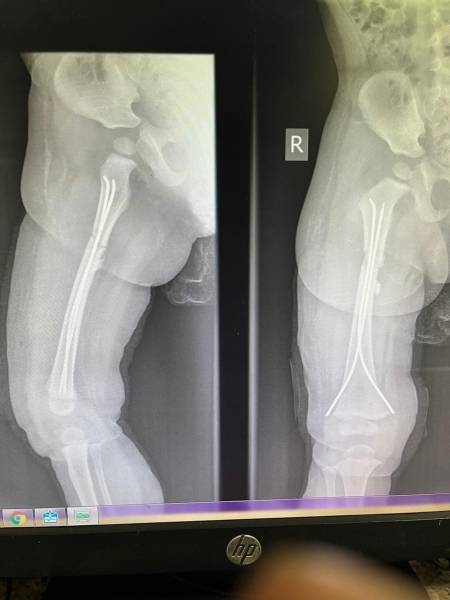

- إجراء عمليات جراحية معقدة و دقيقة في مجال العظام و المفاصل و الكسور و الإصابات ، رغم الضغط الكبير على المستشفى و أعداد المراجعين الكبيرة.

- تطبيق تقنيات جراحية حديثة و متقدمة، و ذلك في ظل التحديات التي يواجهها الفريق بسبب أعداد المرضى و المراجعين الكبيرة.